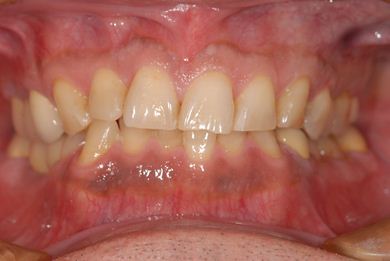

インプラントの症例写真 IMPLANT

インプラント治療+セラミック治療+歯肉歯槽骨整形術

| 主訴 | 悪いところの治療と、歯をきれいにしたい。 | ||||||||||||||||||||||||||||||||

| 治療内容 | インプラント2本、メタルボンドセラミッククラウン9本(メタルボンド用土台6本)、ハイブリッドセラミッククラウン2本(セラミック用土台2本)、ハイブリッドセラミックインレー5本、歯肉歯槽骨整形術 | ||||||||||||||||||||||||||||||||